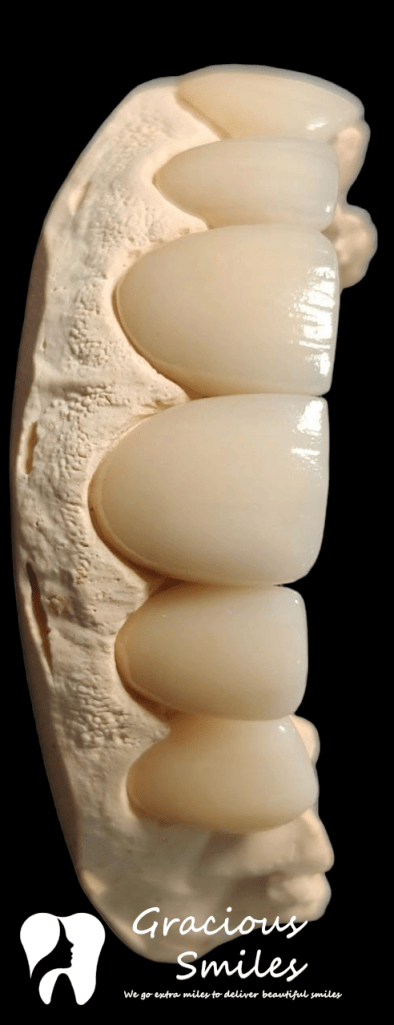

The picture gallery at Gracious Smiles showcases some of the remarkable transformations our patients have achieved through the range of dental treatments. From before-and-after photos of dental implants, Invisalign aligners, and braces to images of successful TMJ treatments, the gallery provides a visual representation of the high-quality care that patients can expect at Gracious Smiles. The photos are a testament to the expertise and dedication of our dental professionals in helping patients achieve their dream smiles.

Ceramic Veneers